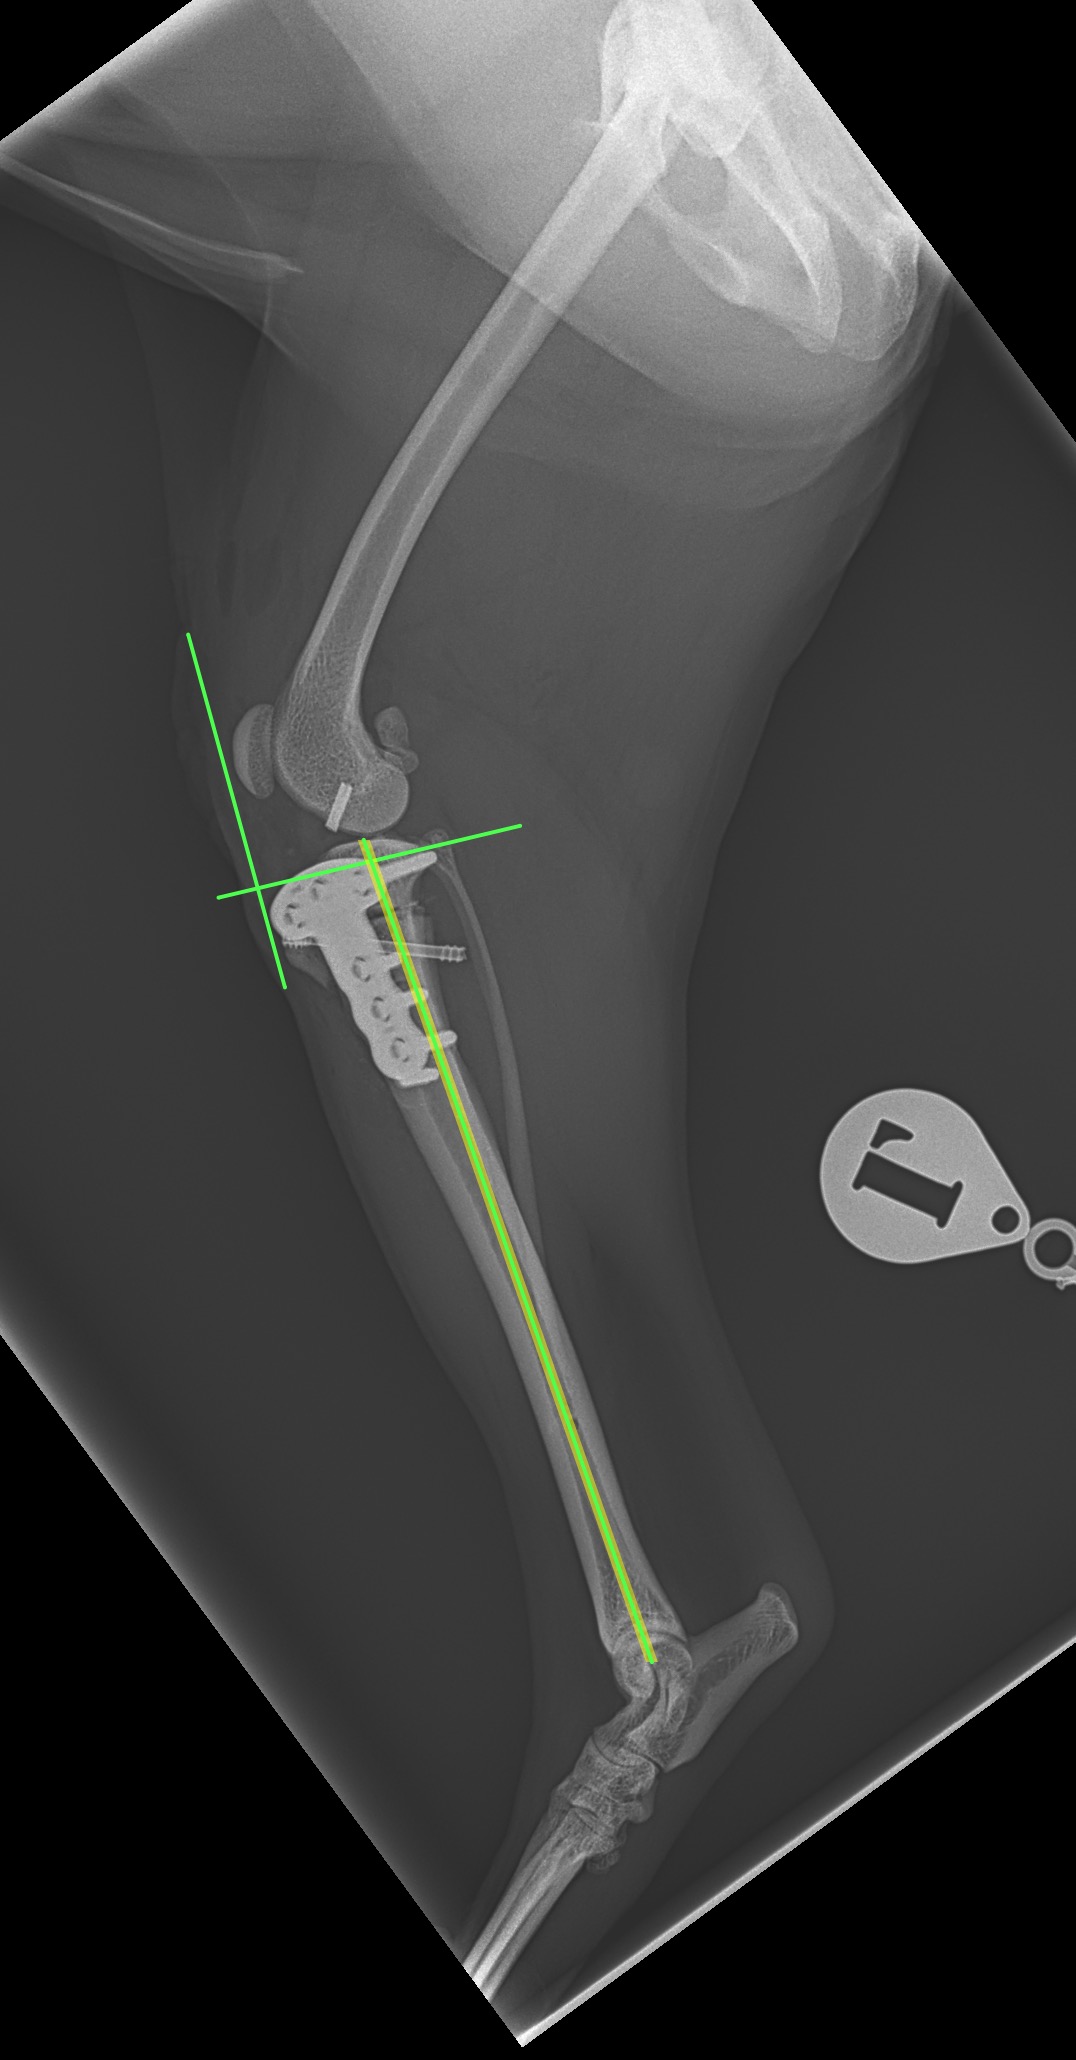

前十字靭帯(完全)断裂に対してCBLO+LSSで対応しました。麻酔下における脛骨ピボット圧迫試験がPositiveであったため、脛骨の内旋矯正のためアンチローテーションスーチャーを追加しています。術中に脛骨の内旋が消失したことが確認されました。前十字靭帯断裂の約30%に術後に脛骨の内旋が残存すると報告されており、術中に不安定性が認められる場合はTPLOやCBLOのみでは脛骨前方スラストは抑制されても、膝の内旋は矯正されないので注意が必要です。